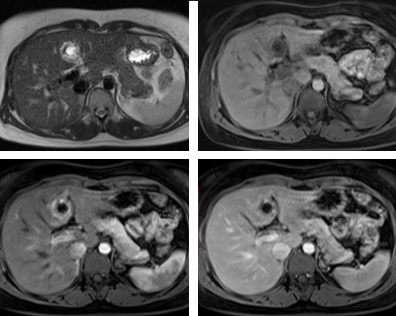

MRI: Gan ở hạ phân thùy IVb có tổn thương 26 x 27 mm, với viền mô đặc dày 6-7 mm ở ngoại vi bao quanh cấu trúc dạng dịch 11 mm. Phần mô đặc có tín hiệu thấp trên T1W, cao nhẹ trên T2W, bắt thuốc tương phản mạnh không đồng nhất. Tổn thương có vị trí nằm rất sát nhánh trái tĩnh mạch cửa. Tĩnh mạch cửa và các tĩnh mạch gan bình thường.

Chẩn đoán MRI: Tổn thương ở hạ phân thùy IVb gan trái, gợi ý thai ngoài tử cung.

Hình ảnh MRI:

Hình 3, 4, 5, 6: theo thứ tự Axial HASTE, T1 FS, T1FS CM thì động mạch và thì tĩnh mạch: cho thấy có khối choán chỗ ở hạ phân thùy IV, cấu trúc: phần ngoại biên tín hiệu mô dày# 6-7mm, bao cấu trúc tín hiệu dịch d# 11mm, phần ngoại biên có tín hiệu thấp trên T1W, cao nhẹ trên T2W, bắt thuốc mạnh ở thì động mạch và vẫn còn tín hiệu cao nhẹ trên thì tĩnh mạch.

Hình 7: Tổn thương nằm sát nhánh trái tĩnh mạch cửa.